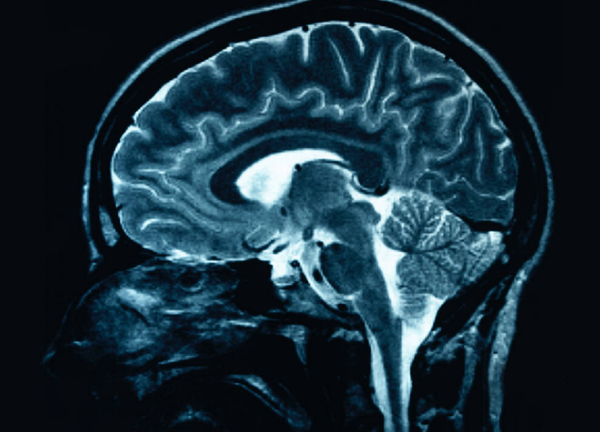

Washington.- Consumir una alta dosis de cocaína provoca la autodestrucción de las neuronas del cerebro mediante la autofagia hiperactiva, un proceso en el cual las células se comen a sí mismas, reveló un nuevo estudio publicado por la revista estadounidense Proceedings of the National Academy of Sciences (PNAS).

Para averiguarlo, el equipo de investigación examinó las células nerviosas del cerebro de los ratones, y concluyeron que éstas también pueden cometer "suicidio" químicamente.

Según explicó Snyder, una forma de hacerlo es la autofagia, un "proceso de limpieza" normal y muy necesario que elimina los desechos de células, pero si este proceso se acelera y se sale de control causa la muerte celular.

Mediante la medición de los cambios en los niveles de proteínas que controlan la muerte celular y observando los cambios físicos de las mismas, el equipo vio claramente que la cocaína causa la muerte celular neuronal a través de la autofagia fuera de control.